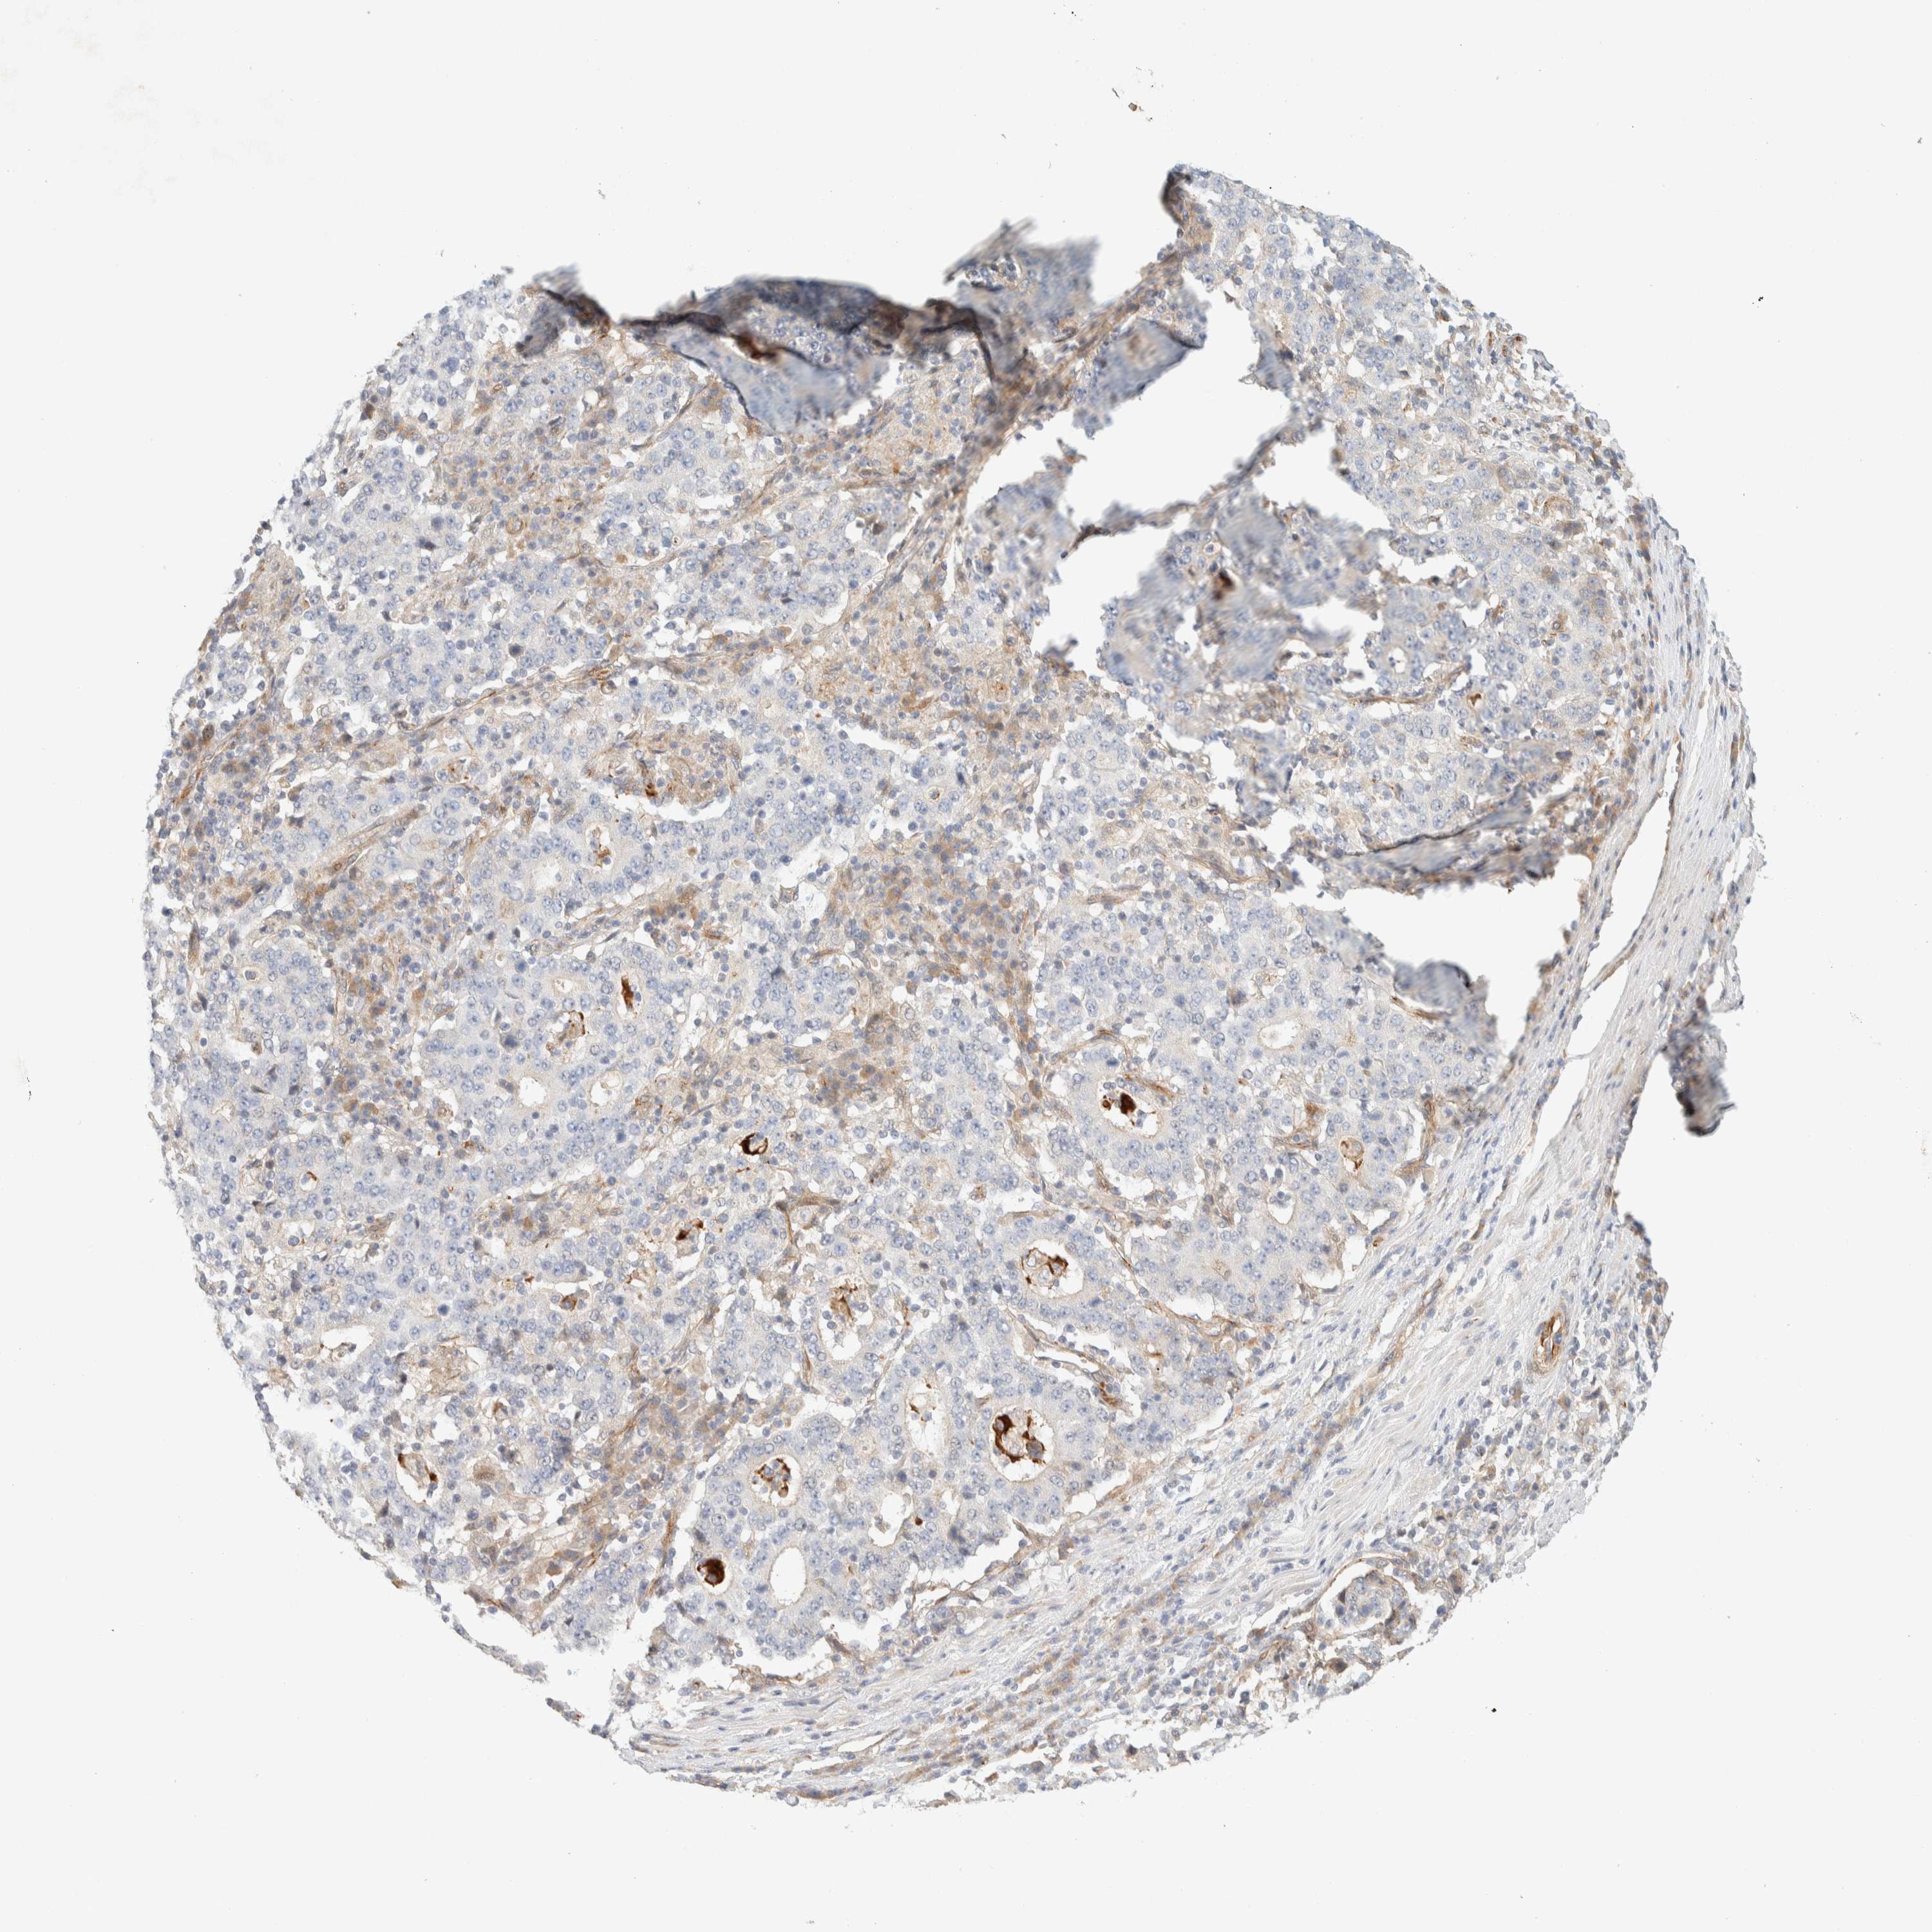

STOMACH CANCER - Protein expressioni

A mouse-over function shows sample information and annotation data. Click on an image to view it in a full screen mode. Samples can be filtered based on level of antibody staining by selecting one or several of the following categories: high, medium, low and not detected. The assay and annotation is described here.

Note that samples used for immunohistochemistry by the Human Protein Atlas do not correspond to samples in the TCGA dataset.

Antibody stainingi

Antibody staining in the annotated cell types in the current human tissue is reported as not detected, low, medium, or high, based on conventional immunohistochemistry profiling in selected tissues. This score is based on the combination of the staining intensity and fraction of stained cells.

Each image is clickable and will lead to virtual microscopy that enables deeper exploration of all samples and also displays staining intensity scores, fraction scores and subcellular localization as well as patient and tissue information for each sample.

Antibody HPA001869

Antibody HPA023882

Staining

High

Medium

Low

Not detected

Intensity

Strong

Moderate

Weak

Negative

Quantity

>75%

75%-25%

<25%

None

Location

Nuclear

Cytoplasmic/membranous

Cytoplasmic/membranous,nuclear

Adenocarcinoma, NOS

Adenocarcinoma, High grade